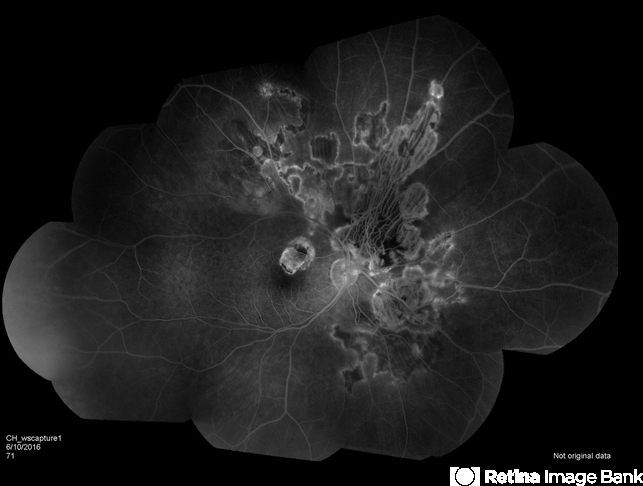

- serpiginous choroiditis

- Fundus camera

- Serpiginous choroiditis.